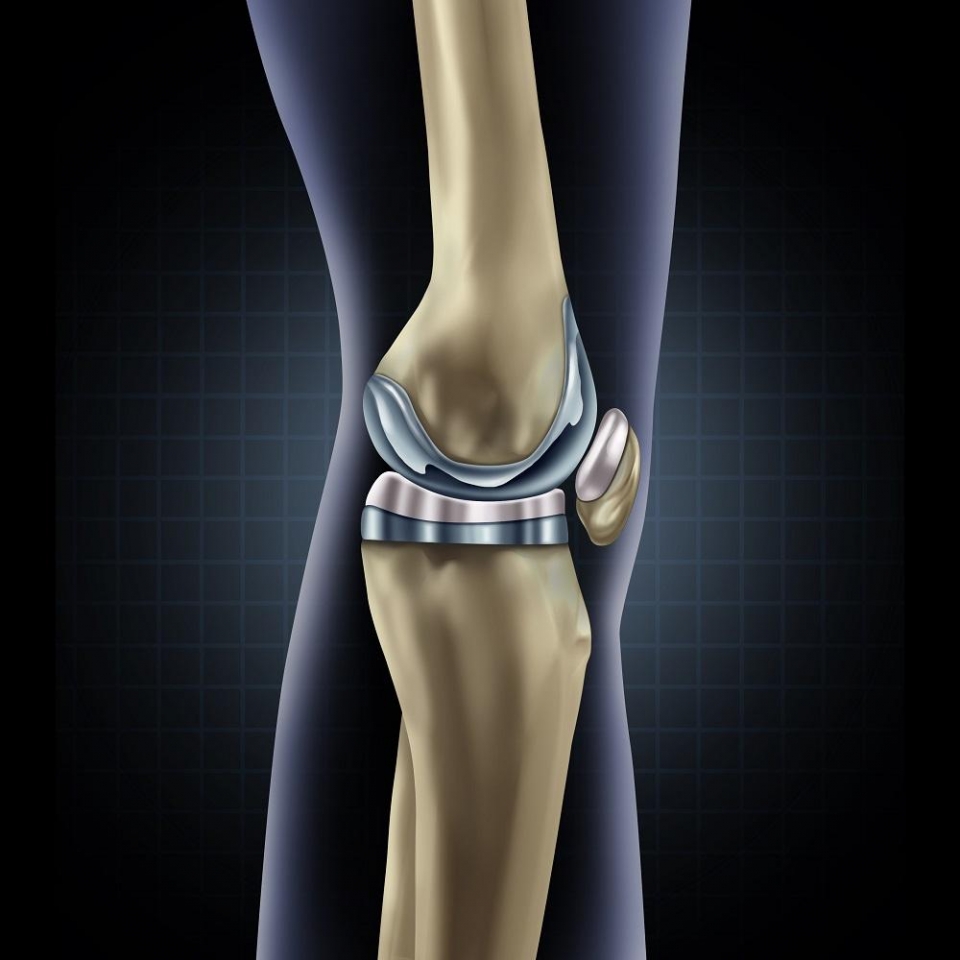

• Χειρουργικής Γόνατος, με έμφαση στην αρθροσκόπηση και ολική αρθροπλαστική